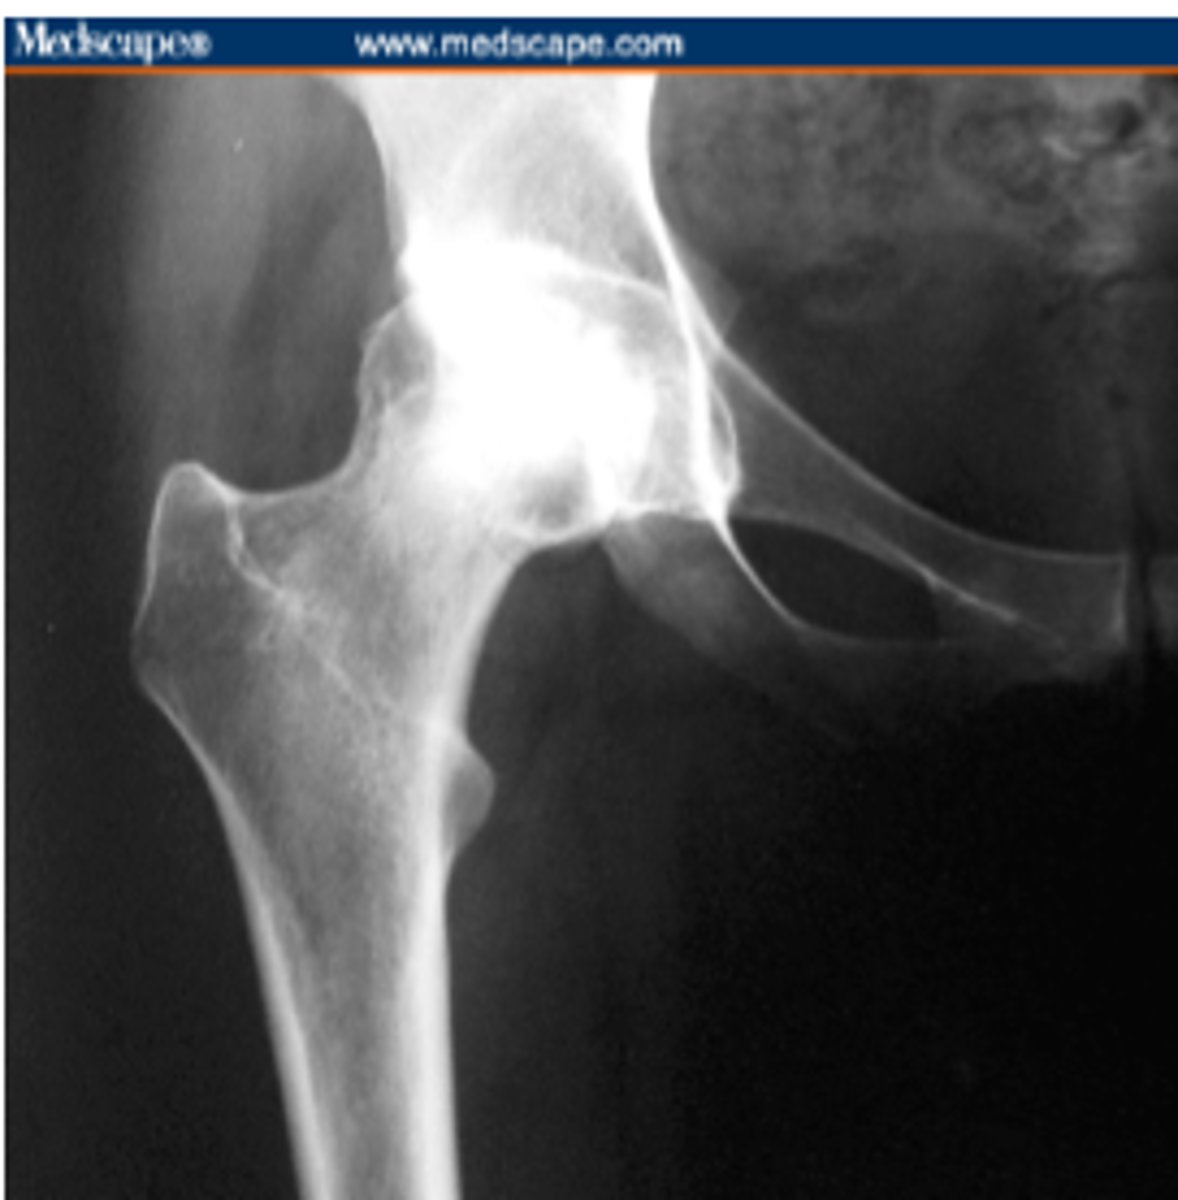

slipped capital femoral epiphysis

gradual or acute failure of the epiphyseal plate of the head of the femur due to shear forces parallel to the growth plate, causing the head to slide posterior/inferior

*may be related to trauma, inflammation, obesity, or hormonal factors

**more likely in males, onset approx 13 yrs of age (10-17)

FUNCTIONAL DEFICITS--> pain, gait changes (antalgic pattern)

COMPENSATORY MOVEMENTS--> may result in growth deficits, complications include avascular necrosis

Legg-Calve-Perthes Disease

a type of osteochondrosis or disease of the growth centers in children which begins as a degeneration followed by regeneration and recalcification

*unknown etiology

**more likely in males, onset is generally 5-7 yrs of age (3-13)

FUNCTIONAL DEFICITS--> pain, limited ROM, gait changes

COMPENSATORY MOVEMENTS--> limit motion/use of the joint, limit overall activity level

COURSE--> bone necrosis, revascularization, reossification over a period of 24-36 months